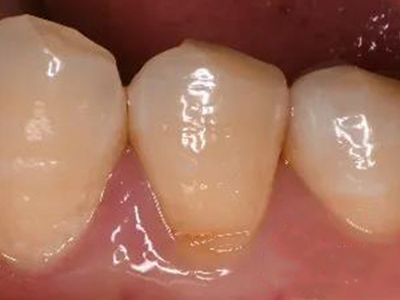

楔状缺损是一种非龋性牙颈部慢性损伤,是指发生在牙齿唇、颊面颈部的慢性硬组织缺损。典型缺损由两个夹面组成,口大底小,呈楔形。楔状缺损多发生于中老年人,主要原因是刷牙不当,防治措施是调整咬合关系,改善刷牙方法,配合相应的治疗。

楔状缺损与年龄相关,即年龄越大,缺损越重,患者多有横刷牙习惯,患牙为多颗甚至全口,常以口角附近的牙齿(尖牙、前磨牙)为重。典型表现为牙颈部缺损,呈楔形,由两个夹面组成,口大底小,缺损处质地坚硬,表面光滑,边缘整齐,无染色,轻微泛黄常为牙齿本色,严重时可导致牙髓腔暴露甚至牙齿横向折断,根据缺损深浅不同,可伴有牙齿敏感甚至疼痛。

如果楔状缺损不深、症状不明显,可以不处理,有过敏症状可进行脱敏治疗。楔状缺损较深者可行充填修复。缺损达到牙髓腔,导致牙髓感染、根尖周病或牙齿横折者,可进行根管治疗、拔除患牙,再进行修复。平时要采取正确的刷牙手法,例如巴氏刷牙法,避免咬硬物。必要时通过正畸、修复等方法调整咬合关系。